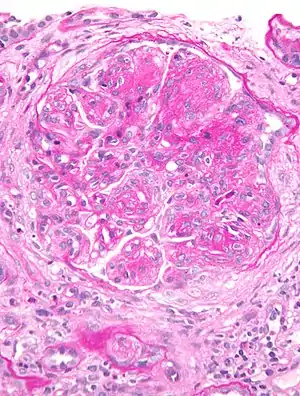

| Micrograph of glomerulus in membranoproliferative glomerulonephritis with increased mesangial matrix and increased mesangial cellularity. Kidney biopsy. PAS stain. | |

The GBM is rebuilt on top of the deposits, causing a "tram tracking" appearance under the microscope.[17] Mesangial cellularity is increased.[18]